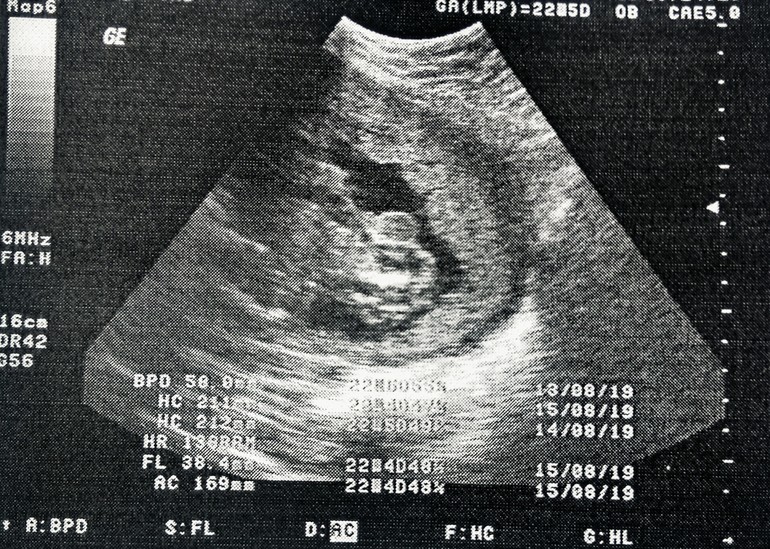

УЗИ на 23 неделе)

Вопросы про УЗИ, обследования и анализы: что, где, как, когда?Девчонки всем привет! Подскажите, сходили мы на УЗИ, врач долго разглядывал на экране, говорит худо видно пипиську из-за пуповины, а потом как то сбоку навел сканер свой, ВО! говорит,смотри какой мужик! Видишь мошонку? Я то от радости заревела)))Мы с мужем хотим мальчика очень. По снимкам думаете правда мальчик? аппарат допотопный конечно стоит 100 лет.

Ну приблизительно вот так было, шевелился постоянно. Ножку как то вверх поднял))) я же говорю аппарат древний,какие уж там 12 недель,на скрининг ездили там только заключение выдали ,что отклонений не выявлено. А так хотелось посмотреть на него. Вот и ждали 23 недели,чтоб хоть пол сказали